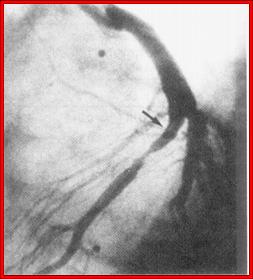

Cardiac Catheterization and Coronary Artery Angiography (Cath or Angio) - These invasive, hospital based procedures allow precise definition of you cardiovascular physiology and coronary artery anatomy - they are our diagnostic "gold standards".  Cardiac catheterization refers to the process of inserting a catheter (a narrow plastic tube - basically a long IV catheter) into a peripheral vessel and advancing it under fluoroscopic (X-ray) guidance into the region of the heart.  The procedure is carried out in a hospital room dedicated to this purpose (the "cath lab").  You arrive at the hospital two hours before the procedure.  An IV is placed within an arm vein and you receive Versed (a short-acting Valium like agent) and Benadryl (to minimize the risk of an allergic reaction to the X-ray contrast dye that we use).  We numb up the skin over the femoral artery and vein, puncture these vessels with a needle, and then through the needle thread a flexible guide wire into the vessels.  The needle is withdrawn and over the guide wire we pass the heart catheters.  Through the catheters we can record the blood pressures within your heart chambers and obtain valuable information not available from non-invasive testing (are you fluid overloaded or volume depleted, do you have pulmonary hypertension on the basis of left heart failure or lung disease, how much blood is flowing through a congenital defect in your heart, etc?).  We can inject X-ray contrast dye into the arteries that serve the heart while obtaining digital X-ray images.  This allows us to define the extent and severity of plaque deposition within your coronary arteries.  Afterwards the catheters are withdrawn and manual (with our fingers) pressure is placed over the puncture site to allow the artery to seal over.  You then lie flat for 1 to 2 hours, and we typically send you home 3 hours later.  With the diagnostic information obtained from the catheterization/angiogram, integrated in to what we know about you from your history, lab profile, and non-invasive testing, we can make our best recommendation as to whether you would benefit from a revascularization procedure, such as angioplasty/stent placement, bypass surgery, laser revascularization, or EECP.  The up side of catheterization is that it the procedure gives us valuable information.  The down side is that it hurts a little (probably a little worse than going to the dentist), and as catheterization/angiography is an invasive procedure, it does expose you to some risk.  The risk of dieing from catheterization/angiography is 1 in 1000 and the risk of a non-lethal complication is 1 in 100.  Here we are talking about stroke or heart attack due to clot formation or plaque dislodgement related to the procedure itself, or damage to the femoral artery at the puncture site (clotting or hematoma - a blood blister - formation).  Your catheterization related risk is related to your age and overall health.  Risk is greater when we are carrying out an urgent angiogram on an 80 year old with unstable angina and pre-existent vascular and kidney disease.  Risk is much, much less when we are carrying out an elective procedure in a younger patient in good health.  The decision as to whether you should or should not undergo catheterization is one that you will make with my guidance.  The key question is whether the value of the information gained from the procedure will be worth the risk associated with the procedure.  Most often the decision is straight forward and easy to make.  Other times we will scratch our heads and consider other options.  In general, if a non-invasive approach will give us the information that we need, then we will not carry out an angiogram.  However, if we feel that you might benefit from an invasive revascularization procedure, than an invasive diagnostic procedure, the angiogram, is mandatory.  A surgeon cannot carry out bypass surgery without an angiogram to guide him - otherwise how would he know where to place the grafts?  You can't be stented based on a stress test alone.  Sometimes, based on my non-invasive assessment, I just can't be sure whether or not you have a blocked artery.  You may not be interested in invasive revascularization, but before we spend a great deal of your out-of-pocket money on non-interventional, complementary approaches, shouldn't we also definitively determine whether you do or do not actually have a blockage?  Many of you are fearful of the angiogram, not just over the risk associated with the procedure, but over what will come next.  You are fearful that once we get you into the hospital setting, that we will not let you go without an invasive revascularization procedure.  This fear is justified.  If a narrowing is found, pressure was placed on me to recommend a stent or bypass surgery.  Pressure will be placed on you to undergo a procedure.  The people who work in our hospitals are all good people, but the only approach to cardiovascular disease that they know about is invasive/interventional.  This is what they do, day in and day out.  This is what they are good at.  They work hard and they help people so this is their approach to cardiovascular care.  They do not know anything about chelation therapy, EECP, MME, IV phosphatidylcholine therapy, mitochondrial support or homeopathy.  They don't know the first thing about these modalities and are convinced that these complementary techniques cannot help you.  They feel that the only way to get better is via an invasive approach.  You may hear something like - "If you leave the hospital without bypass surgery you will have a heart attack and die".  I know what they say because this is what I said to patients over the first 10 years of my career.  I said this because I didn't know that other (and often better) options were available - but now I do.  I will recommend an invasive procedure if my need to know outweighs the risks (to you as an individual) associated with the procedure.  I have carried out thousands of invasive cardiac studies, but as my focus shifted away from crisis management and towards dealing with the causes of vascular disease, the number of my patients requiring angiography steadily decreased. I also became uncomfortable with the way I was being treated by doctors, nurses, and hospital administrative staff (the wonderful exception here are the nurses at the Toledo Hospital Catheterization Lab - all skilled, professional, and pleasant people to work with) so I quit carrying out angiograms and left the hospital forever.  If you are my patient and I feel you need an invasive study, I will organize your records and communicate in writing with an invasive cardiologist who I trust. They will carry out your angiographic study, then proceed with stent placement or referral for bypass surgery, if these steps are appropriate. I will receive a report and then get re-involved in your care following your recovery.

Intravascular Ultrasound (IVUS) - The coronary angiogram gives us a silhouette of the artery.  We define percent stenosis, the severity of the blockage, as our estimate of the degree of narrowing related to an adjacent region of the artery that is normal.  This is a subjective assessment.  I tend to "under-read" in comparison to the interventional cardiologists and cardiac surgeons who I work with.  There is an old adage that in cardiology there are "under readers" and "over readers" and no "perfect readers".  This is true.  Our perception on your angiogram will be based on how we were trained to read angiograms.  We often disagree a little, but what is important is that we are internally consistent (we interpret your angiogram films the same way, every time).  Often we will pull up your old films and compare your current study with a previous exam (an apples to apples comparison).  There are times, however, when we just can't be sure as to the severity of a narrowing.  Perhaps the narrowing is on a bend or the artery is overshadowed by another vessel.  Sometimes the entire artery is diseased, such that we do not have a "normal vessel" reference point against which to compare the narrowing under question.  In these situations, when we have an important decision to make (should you or should you not undergo bypass surgery?), I may recommend that you undergo an IVUS procedure.  Here the heart catheter has a tiny echo crystal at its tip.  A small region of the vessel (the region of vessel at the tip of the catheter) can be precisely studied by ultrasound.  A precise percent narrowing of the narrowing in question can be determined.  The IVUS catheter is relatively large, and as such can only be used to quantitative proximal (at the beginning of a vessel) narrowings.  It is typically used when we cannot determine from the angiogram alone whether you have a significant narrowing in the Left Main or Left Anterior Descending coronary arteries.